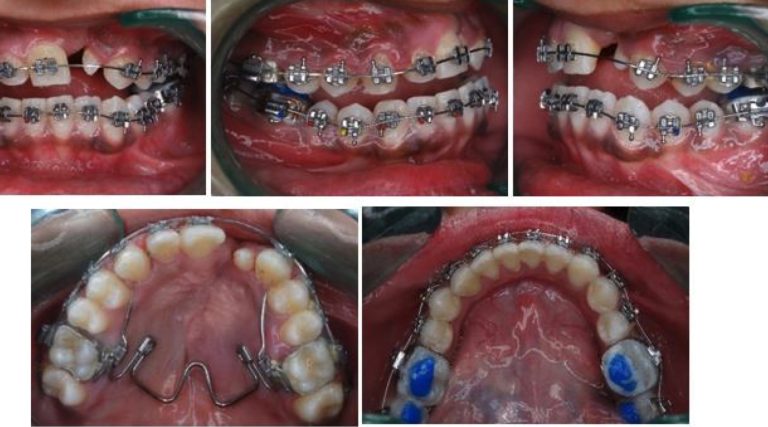

Tratamiento ortopédico de una maloclusión de clase III con mordida cruzada anterior profunda y discrepancia transversal

El artículo que compartimos el día de hoy con uds se llama Orthopedic Management of a Class III Malocclusion With Deep … [Leer más...] acerca de Tratamiento ortopédico de una maloclusión de clase III con mordida cruzada anterior profunda y discrepancia transversal